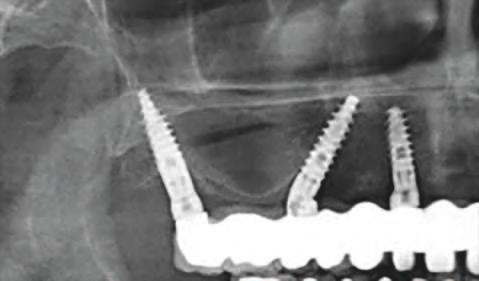

osoasă pentru max larele atrof ate. Un mplant d stal încl nat poate perm te ut l zarea unu a ma lung ș obț nerea une poz ț onăr ma poster oare a acestu a. Teor a d n spatele acestu concept cons deră că d stanțele ma mar între mplantur le anter oare ș posteroare ar d str bu ma b ne forțele ocluzale; astfel, forța transversală exerc tată asupra mplantur lor încl nate nu ar f noc vă pentru acestea. La max lar, mplanturle d stale ar putea benef c a, de asemenea, de pereț osoș cort cal a s nusur lor ș foselor nazale. Pr n urmare, mplantur le pot f plasate cu or entăr încl nate, în loc de ax ale, pentru a angaja osul cort cal rez dual în toate d recț le, cum ar f în palat, pereț anter or ș poster or a s nusulu max lar ș tuberoz tatea max lară. Implantur le încl nate, cu d verse des gnur macro se pot adapta, de asemenea, la osul anatom c nonalveolar în reg un le paranazale/ nterantrale ș pter gomax lare, precum ș la osul z gomat c (f g. 3).

Figura: 3. Implanturile înclinate pot să se adapteze la osul non-alveolar în regiunea interantrală și pterigo-maxilară pentru a evita o procedură de grefare a sinusului.